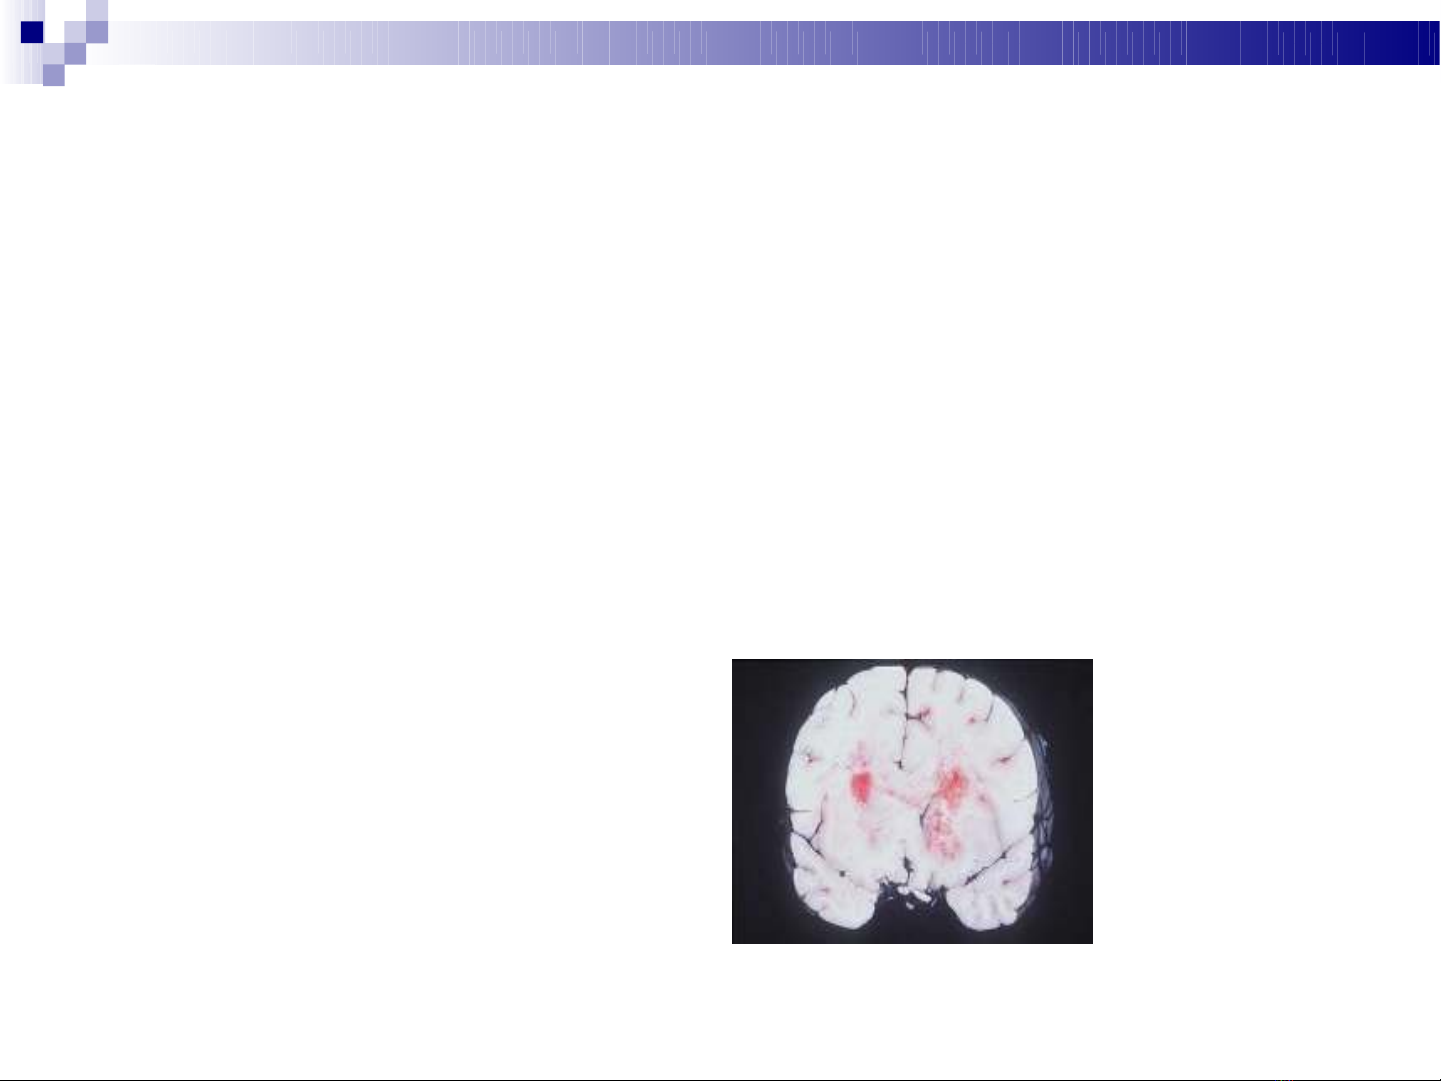

Glioblastoma multiforme highly malignant and invasive